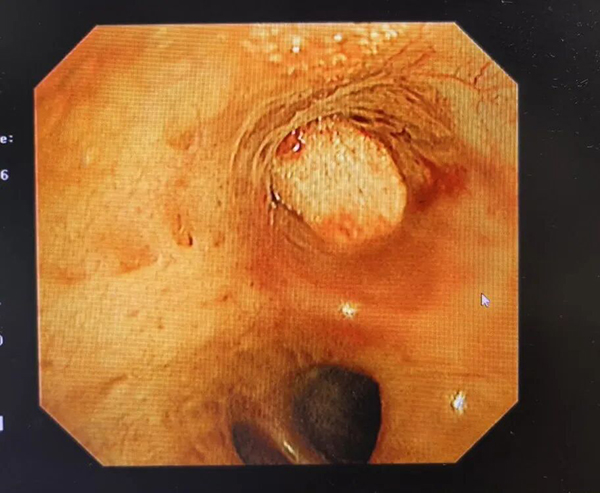

术中,史广林在气管镜的精准引导下,经过球囊探查,找到漏气点支气管,随即注入患者自身的静脉血,再注入凝血酶使得自体血在管腔内迅速凝固,接着置入膨胀海绵,如同给充满混凝土的管道再加上一个“塞子”,将瘘口严丝合缝地堵住。

(因带管时间过长并发脓胸、胸腔感染,胸腔镜下见脓液与坏死组织)

面对病情波动,史广林团队迅速行动,在胸腔镜下细致清除了胸腔内的脓液与坏死组织,为肺复张创造了洁净环境。随着感染得到控制,李老伯的恢复进程明显加快。